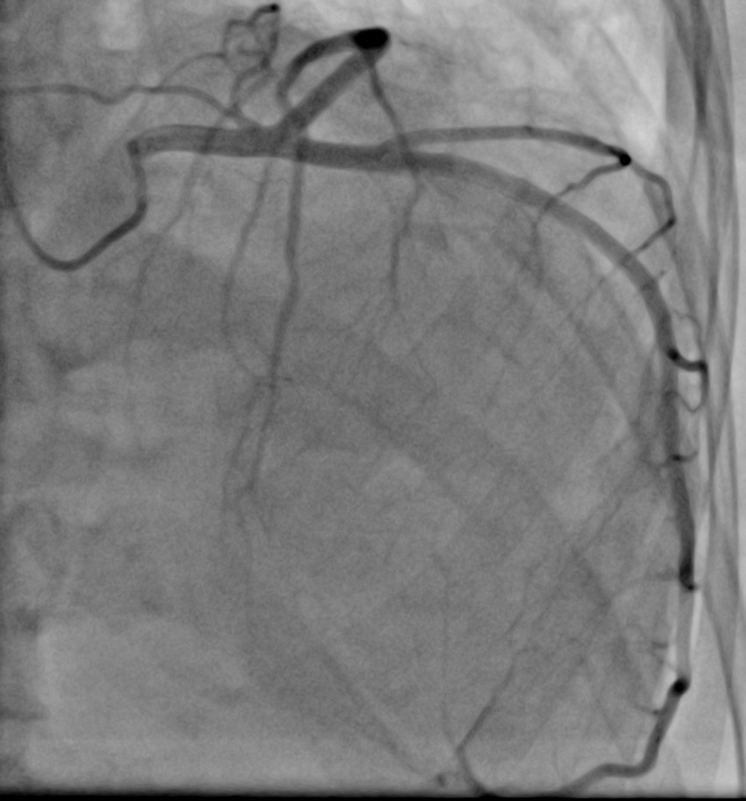

Presentation Case: A 53-year old woman presented with chest pain to the emergency room. Troponin was positive. The ECG showed complete left bundle brunch block. The chest x ray demonstrated levocardia of the heart. Cardiac catherization showed smooth unobstructed coronaries with normal anatomy. However, ejection fraction (EF) was extremely reduced with an EF of 20%. Myocardial biopsy showed no evidence of myocarditis or dilated cardiomyopathy.

Fig 4: Cardiac catherization: smooth unobstructed coronaries